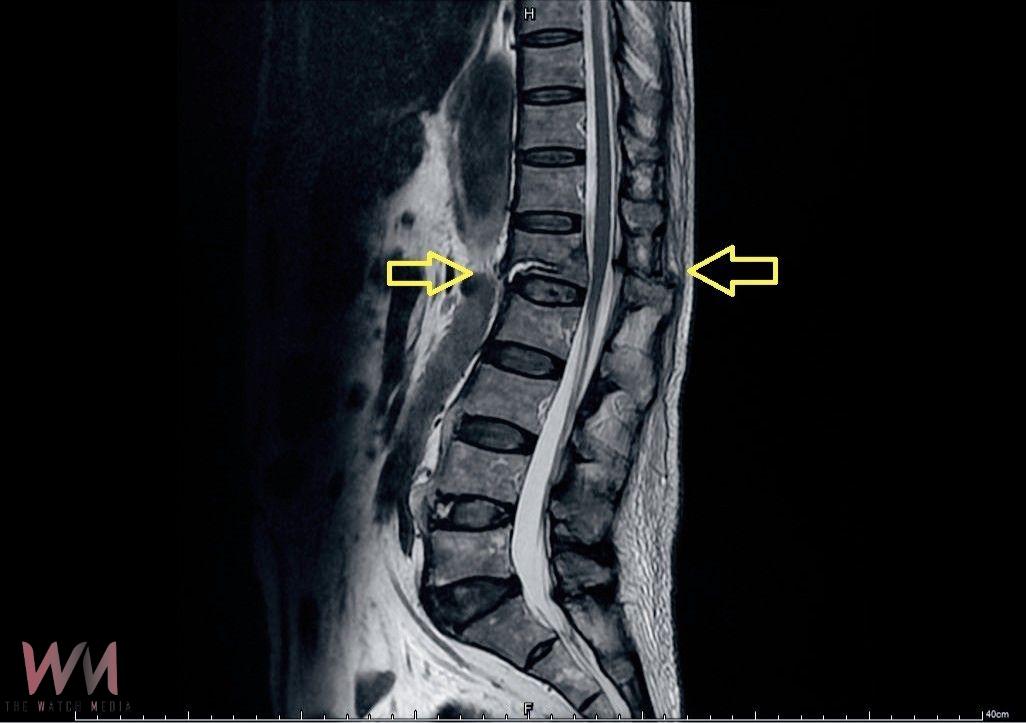

喻大久醫師表示,僵直性脊椎炎是一種慢性發炎性疾病,會使脊椎逐漸融合,變得僵硬且失去彈性。在這樣的情況下受到外力撞擊或是跌倒時,比起一般老年人常見的脊椎壓迫性骨折,容易出現更為嚴重的屈曲牽張性骨折。

喻大久醫師進一步說明,脊椎的穩定結構分成前、中、後三個部分,而屈曲牽張性骨折是這三個結構全都受到破壞。前方椎體因彎曲力量而壓迫,後方的脊突及韌帶則因拉扯而斷裂,進而導致脊椎的不穩定。若不即時處理,可能會造成骨折移位而壓迫到神經,造成坐骨神經痛甚至出現下肢癱瘓。

幸運的是,張先生並未出現神經壓迫症狀,下肢肌肉力量與知覺皆正常。考量到脊椎不穩定的危險性,喻醫師迅速幫張先生安排從胸椎第十節到腰椎第四節的微創脊椎固定手術。相較傳統手術,微創手術僅需在脊椎釘入口處開小傷口,最大程度保留肌肉及周邊組織。此外,手術中也搭配了電腦斷層導航系統,提高手術精準度及縮短手術時間,不僅能大幅減輕術後疼痛,也讓患者恢復速度更快。